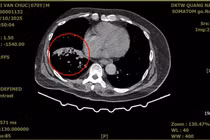

Tại Bệnh viện Đa khoa Hùng Vương, trẻ được khám và làm các xét nghiệm chuyên sâu, xác định áp xe cơ thắt lưng trái - tình trạng nguy hiểm, có nguy cơ nhiễm trùng huyết nếu không xử trí kịp thời.

Đội ngũ bác sĩ nhanh chóng hội chẩn liên chuyên khoa, xây dựng phác đồ điều trị tối ưu, tiến hành dẫn lưu ổ abcess và sử dụng kháng sinh theo kháng sinh đồ.

Theo bác sĩ, áp xe cơ thắt lưng (hay còn gọi là áp xe cơ thắt lưng-chậu) là tình trạng tích tụ mủ trong cơ thắt lưng - chậu, gây ra các triệu chứng như đau lưng, sốt và khập khiễng. Bệnh có thể do lây nhiễm từ các vùng lân cận như cột sống, đường ruột hoặc đường tiết niệu-sinh dục, hoặc do nhiễm trùng từ xa lan qua đường máu. Đây là cơ nằm sâu trong cơ thể nên có thể chẩn đoán muộn hoặc nhầm lẫn với những bệnh học khác. Việc chẩn đoán chính xác và điều trị kịp thời bằng kháng sinh kết hợp dẫn lưu mủ là rất quan trọng để tránh các biến chứng nguy hiểm.